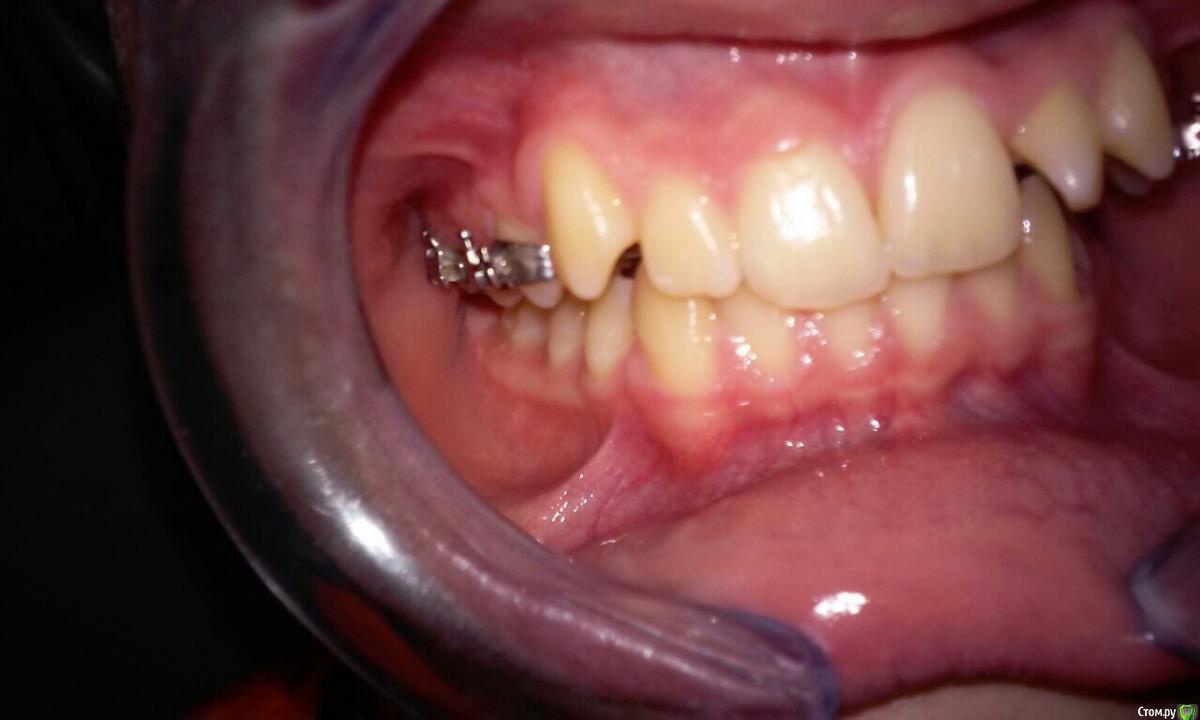

natkoorth1991 Опубликовано 28 августа, 2015 Поделиться Опубликовано 28 августа, 2015 мальчик, 13 лет, премоляры удалять не хотели, поставила хайракс на в / ч- получила перекрестную окклюзию. Извините за плохие фото( Что теперь делать? фото после: Ссылка на комментарий

Yana guapa Опубликовано 29 августа, 2015 Поделиться Опубликовано 29 августа, 2015 конечно, показаний для PRE здесь не было. но раз уж поставили, то поставили.Я бы теперь скручила винт в обратную сторону. будет нужный результат. Потом сняла бы аппарат и просто сделала бы перерыв. Премоляры сами немного вернуться к исходному положению Нет ТРГ. Но стакой инклинацией верхних центральных резцов могу предположить, что НЧ смещена кзади. Если это выяснится, и в ходе лечения НЧ будем перемещать вперед, то это тоже поспособствует лучшему смыканию. ждем снимков 2 1 Ссылка на комментарий

Yana guapa Опубликовано 29 августа, 2015 Поделиться Опубликовано 29 августа, 2015 брекеты на вч не ставить пока? или зафиксировать и раскручивать обратно. По моделям там есть смещение нч где-то на половину бугра. На трг отправлю.я бы не ставила.разберитесь с одной пролемой вначале. чтобы не получить новых. 1 1 Ссылка на комментарий

Maverick Опубликовано 29 августа, 2015 Поделиться Опубликовано 29 августа, 2015 Хайрекс был не по показаниям. Обычная брекет система с этим справилась бы прекрасно. Снимайте его. Пока костная мазоль не образовалась переживать не надо, а это обычно занимает 4-5 месяцев, сняв аппарат получите рецидив и все вернется на круги своя. Либо как предложили выше скручивайте назад такими же темпами. Брекеты не ставьте пока не получить изначальную форму дуги, ну или близкую к ней. Трг это конечно хорошо, но надо смотреть на профиль - это показатель лечения, слепо доверять цифрам не совсем хорошая идея. Лечим не цифры, а людей. 2 1 Ссылка на комментарий